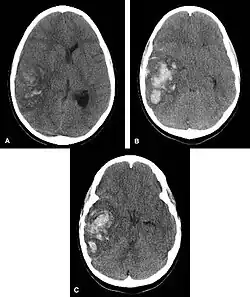

Multiple intraparenchymal hemorrhage

Intraparenchymal hemorrhage

CT-scan of intraparenchymal hemorrhage

Computed tomography (CT scan): A CT scan may be normal if it is done soon after the onset of symptoms. A CT scan is the best test to look for bleeding in or around your brain. In some hospitals, a perfusion CT scan may be done to see where the blood is flowing and not flowing in your brain.